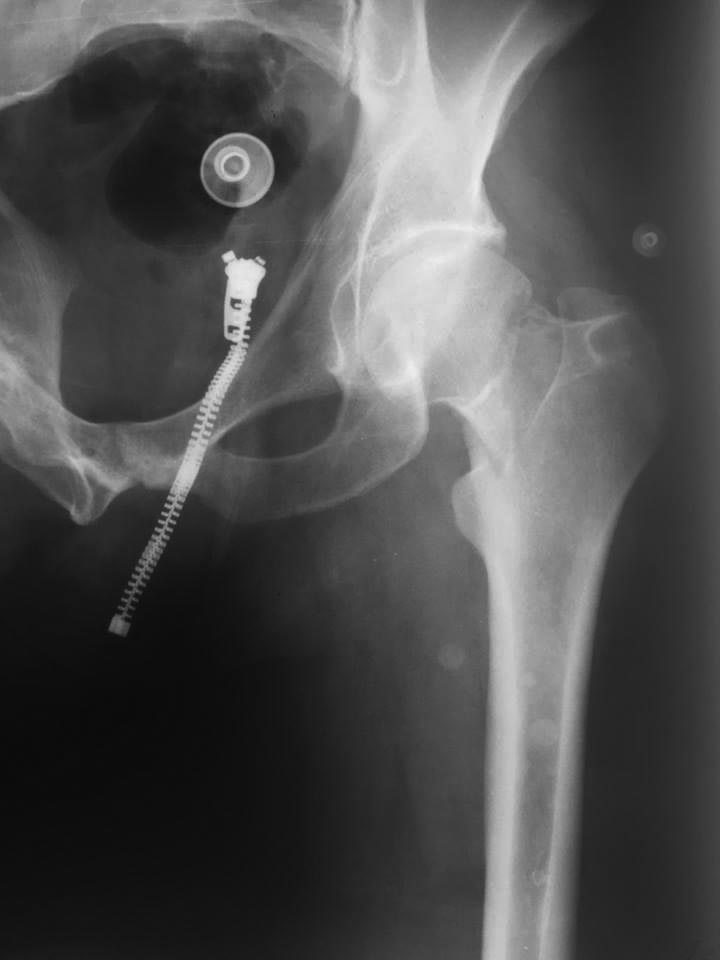

Targon FN не доступен. Есть DHS, винты и вот такая Гамма:

Да и перелом ближе к варусному, на мой взгляд, фиксация тут чревата даже и у социально адаптированного больного

Да, перелом "ближе к варусному". Это означает, что для остеосинтеза следует воспользоваться не винтами, с которыми вирусный коллапс случается при вертикальном переломе в 40-50%. А имплантатом с фиксированным шеечно-диафизарным углом, что этот риск уменьшит до 3-5%.

Необходимо выполнить аксиальный снимок или КТ. Предварительно - данный перелом по классификации Павелса относится к 3 типу т.е. преобладают силы скольжения, учитывая медиальный характер перелома предпочтение нужно отдать эндопротезированию. Учитывая социальный фактор можно ограничиться однополюсным протезом. Велика вероятность что через год после остеосинтеза пациент может вернуться в связи с отсутствием консолидации и аваскулярным некрозом головки и будет необходимо тотальное эндопротезирование.

Несмотря на небольшой варус, на рентгенограмме не так уж плохо. По линии перелома имеется уплотнение и это доказывает что перелом имеет impacted компонент, т.е.“вколоченный”. Поэтому перед тем, чем выяснить сможет ли больной выдержать ортопедический режим, надо его дообследовать. Обычный аксиальный снимок или КТ срезы точно укажут стабильный перелом или нестабильный. При сомнениях можно сделать stress test или EUA-Evaluation Under Anesthesia под рентген контролем. Другой простой метод: пару дней наблюдать клинически, следить за появлением боли при Log Roll Test или сделать контрольный снимок после костылей! Если перелом стабильный, тогда больного можно отпустить с полной нагрузкой, потому что любая нагрузка по оси благоприятно влияет на сращение! А профилактическая фиксация каннюлированными винтами ускорит восстановление!

По поводу предложенного Гамма-3, хотя фиксатор разработан исключительно для фиксации чрезвертельных переломов, но при отсутствии менее сложных, можно фиксировать перелом шейки бедра. Хотя фиксатор проявляет лучшие механические свойства при чрезвертельных переломах, создает максимальную стабильность, где можно начать нагрузку с первого дня. Нагрузка идет за счет lagging screw в головке и бедренного компонента, т.е. распределение сил минуя перелом проходит между головкой и диафиз!

Предложенная техника установки Гаммы ради простого перелома шейки чересчур сложная. Надо отработать специальную технику: временная спица, повороты на спине и на бок, все эти трюки усложняют установку! При этом меняется вектор нагрузки, а перелом шейки требует создание компрессии в зоне перелома, т. е. за счёт телескопии или равномерно расположенных параллельных винтов внутри шейки! Механические исследовании показали, что параллельно расположенные винты по внутреннему краю диаметра шейки создают лучшие условия для стабильности, чем одинокий винт DHS в центре!

Все остальные предложенные фиксаторы повторяют те же принципы, так что трудно рекомендовать для фиксации на шейке. Например Intertan от Smith&Nephew засчет сверления в проксимальном отделе бедра оставляет огромный дефект, потому что для создания стабильности надо просверлить проксимальный отдел бедра до 16.25мм. Фиксатор очень стабильный и хорошо зарекомендовал у пожилых, где имеется остеопения, а у молодых нет смысла потери большого количества кости! Потому что даже идеальная фиксация не гарантирует 100% сращение и к костям нужно относится бережно для следующих реконструктивных операции. Мини инвазивный принцип, обычные каннюлированные винты в 6.5мм являются идеальным для перелома шейки!

А непослушное поведение больного связано с его заболеванием-алкоголизмом и наказание, кокситной повязкой немного жестковато и не выход из положения! Перелом шейки без смещения, а в молодом возрасте протез слишком агрессивный подход!